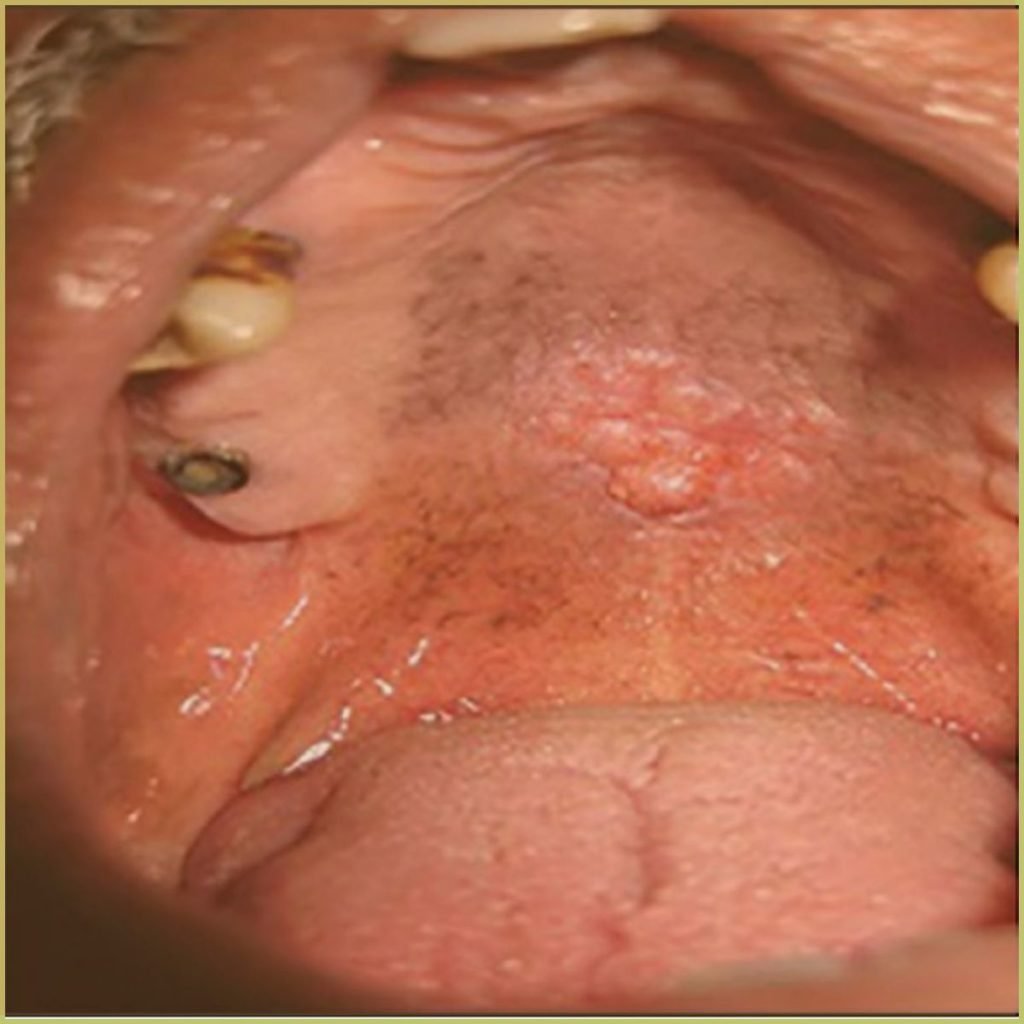

HISTOPLASMOSIS

Histoplasmosis is a fungal infection caused by Histoplasma capsulatum which is endemic to the Ohio and Mississippi River valleys. Transmission is via spore inhalation, leading to pulmonary lesions with possible dissemination to secondary sites. Most infections are subclinical and self-limiting in immunocompetent patients. Organ involvement due to disseminated histoplasmosis can be fatal if untreated. The common clinical presentation includes:

- Chronic ulcerations with necrosis.

- Elevated nodular margins around ulcers that may resemble squamous cell carcinoma.

- A cobblestone appearance on the tongue

Diagnosis is based on the lesion history, clinical presentation and serological findings or culture analysis. Your differential diagnosis should include:

- Tuberculosis.

- Squamous cell carcinoma or other malignancy.

- Other deep fungal infections (coccidioidomycosis, cryptococcosis, and blastomycosis).

- Chronic traumatic ulcer.

- Tertiary syphilis.

- Crohn’s disease.

Treatment options include various antifungal agents (Amphotericin B, ketoconazole, fluconazole, itraconazole). The condition may be self limiting and the prognosis is generally good.